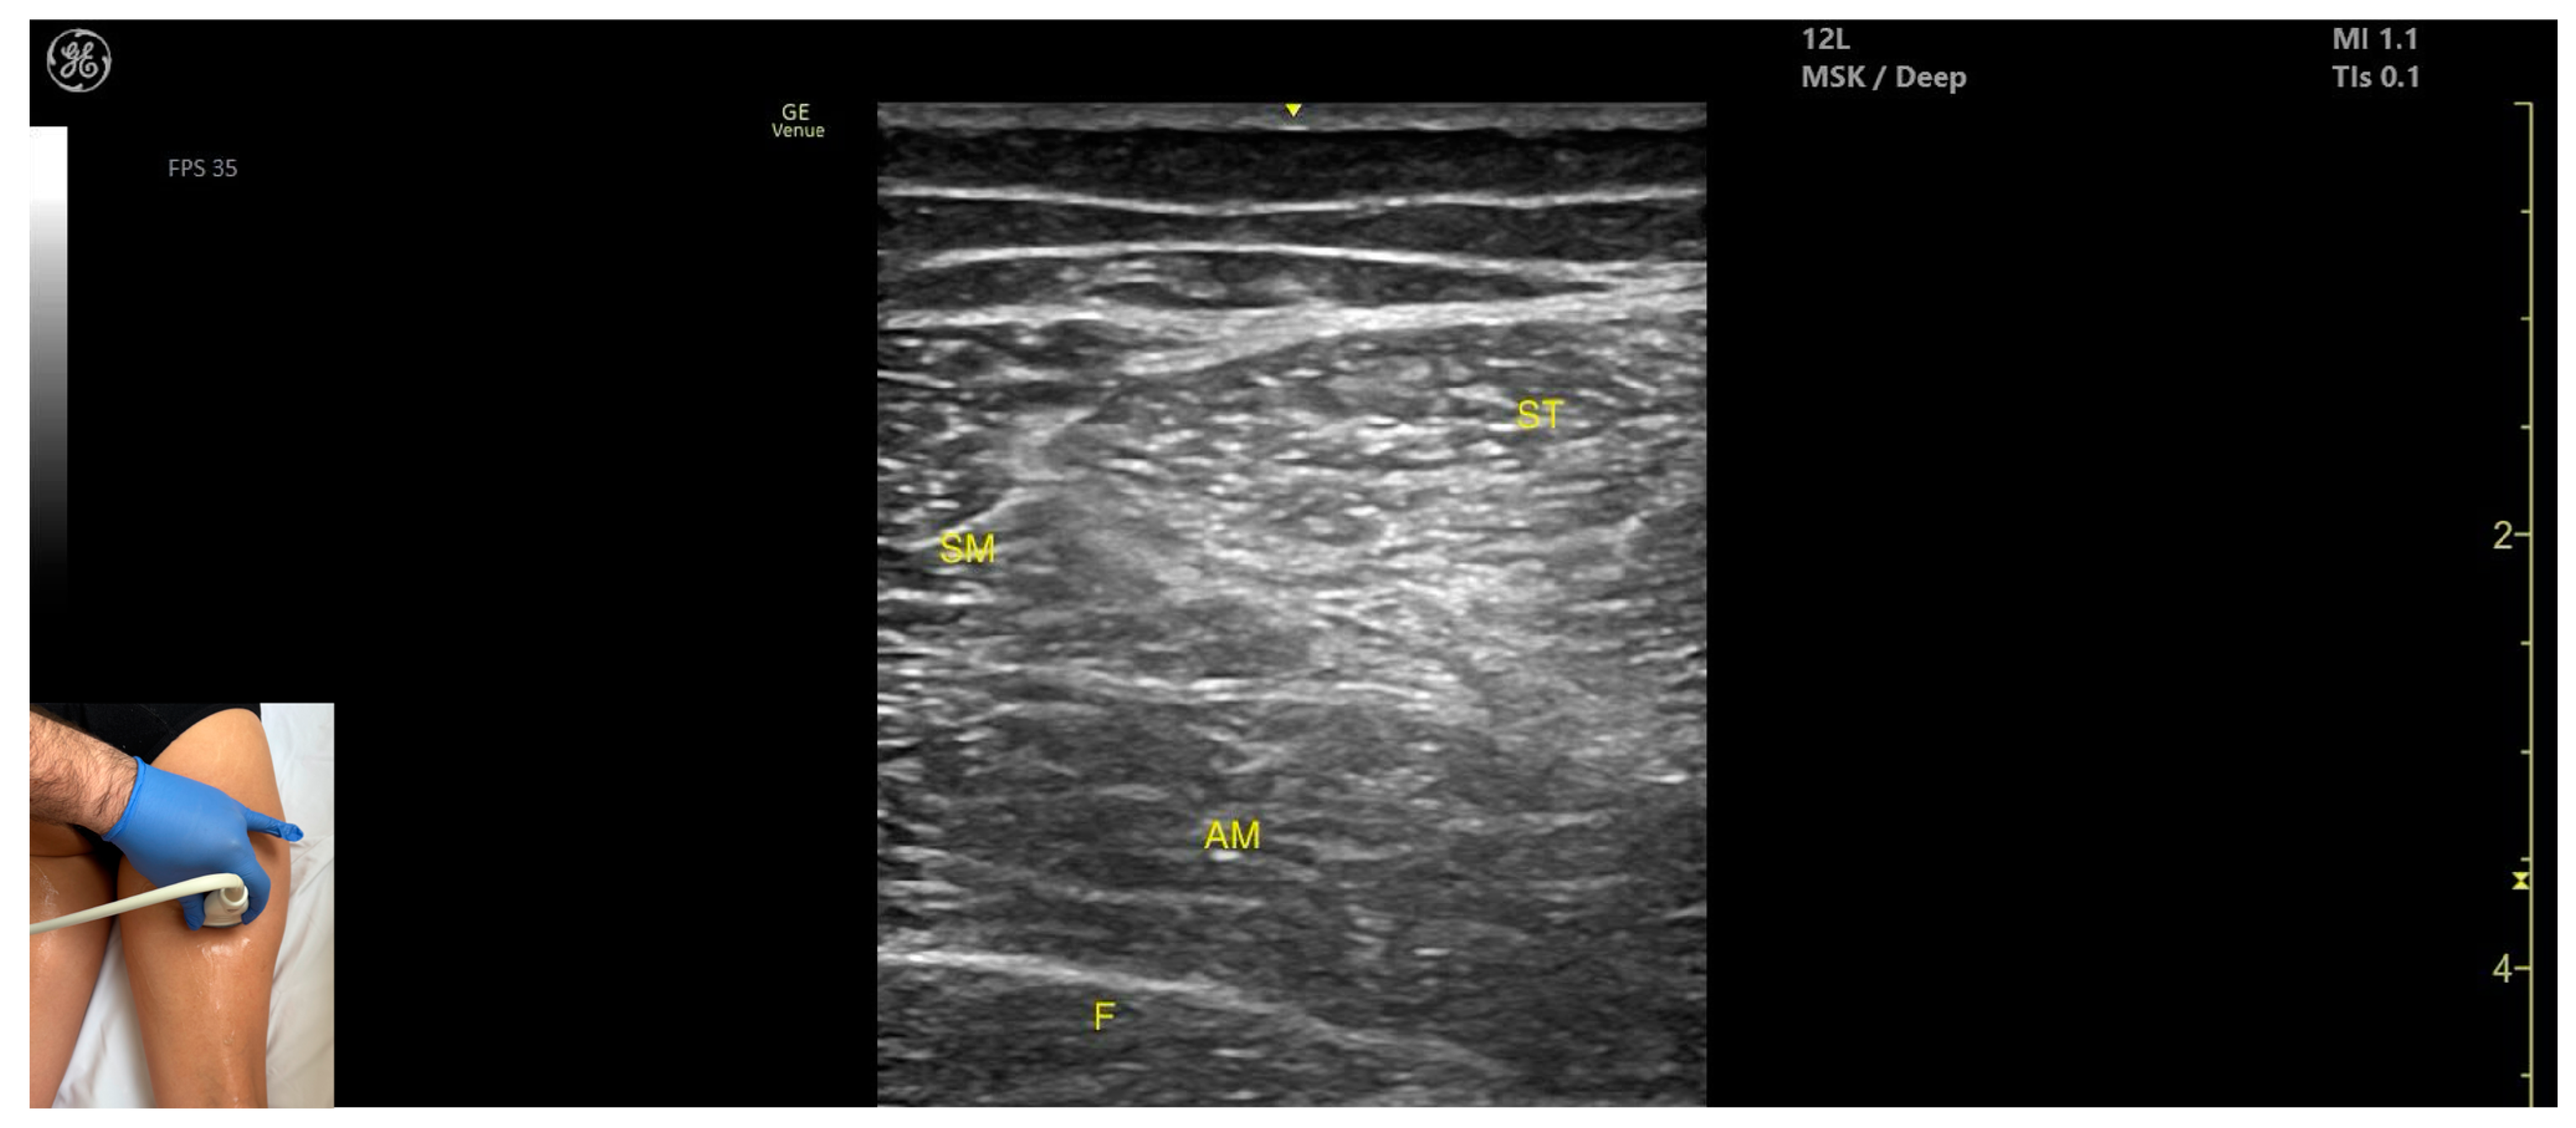

3.9. Semimembranosus (SM)

3.9.3. Key Ultrasound Landmarks

- Muscle position: It is a superficial muscle mass at this level. It is the first muscle seen from medial to lateral on the posterior surface of the thigh. Deep and medial to it lies the adductor magnus, while laterally to it lie the semitendinosus and biceps femoris muscles. The sciatic nerve is located deep and lateral to the SM and semitendinosus and deep to the biceps femoris. The popliteal vascular bundle is visualized deep to the muscle in the distal third of the posterior thigh.

- External fascia: It has a pronounced fascia that separates it from the subcutaneous tissue, semitendinosus, and adductor magnus, aiding in safe botulinum toxin injection.

- Dynamic evaluation: During dynamic evaluation, scanning proximally toward the hip joint, the SM decreases in thickness, while the semitendinosus increases; the sciatic nerve remains lateral and deep to the semitendinosus. Contraction is visible during hip extension, knee flexion, and the internal rotation of the leg.

3.9.4. Clinical Implications and Injection Strategy

3.10. Semitendinosus (ST)

3.10.3. Key Ultrasound Landmarks

- Muscle position: It appears as a superficial muscle mass at this level. It is the second muscle from medial to lateral in the proximal third of the posterior thigh. It is bordered medially by the semimembranosus and laterally by the biceps femoris. The sciatic nerve lies deep and lateral to the ST and deep to the biceps femoris.

| SM | Semimembranosus (muscle) |

| ST | Semitendinosus (muscle) |

| Semimembranosus | Distal third of posterior medial thigh | Semitendinosus (lateral), adductor magnus (deep and medial), sciatic nerve (deep and lateral), and popliteal bundle (deep) | Transverse scan on posterior medial thigh | Avoid neurovascular structures in distal thigh |

| Semitendinosus | Proximal third of posterior medial thigh | Semimembranosus (medial), biceps femoris (lateral), adductor magnus (deep), and sciatic nerve (deep and lateral) | Transverse scan on posterior thigh | Visualize characteristic ’Mercedes-Benz’ and ’Venetian blind’ signs, avoid nerve injury |